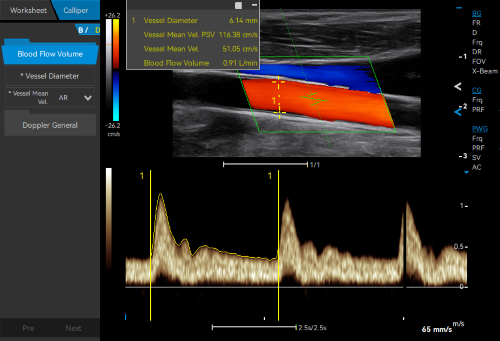

VS Flow is highly sensitive to low velocity blood flow signal and especially suitable for superficial blood flow examination

Auto Flow automatically adjusts the sampling frame to better capture the blood flow signal, while Auto Fit intelligently optimizes the image display through one click